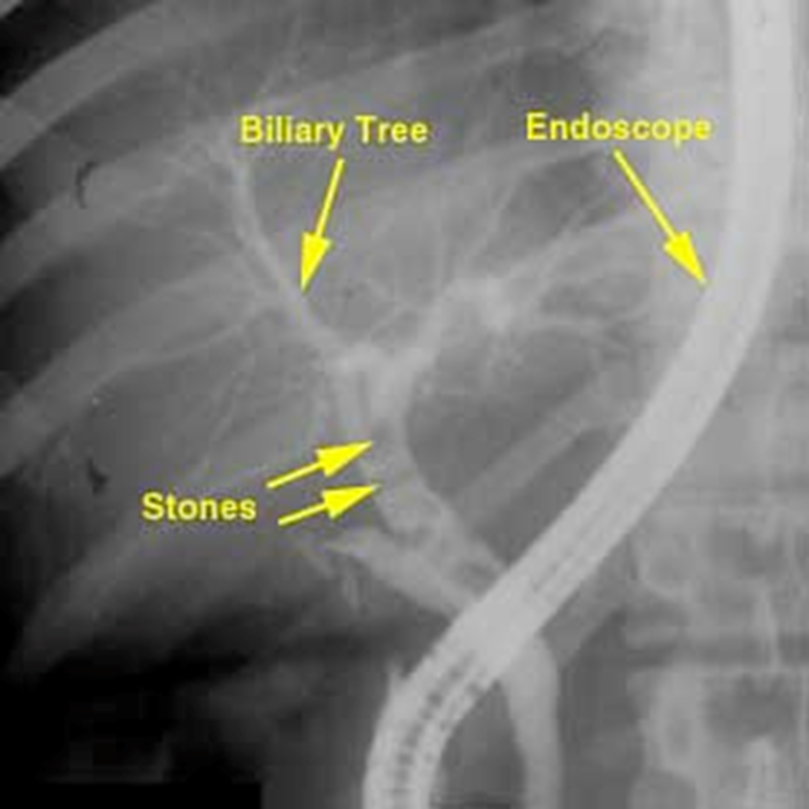

Endoscopic Retrograde Cholangiopancreatography (ERCP)

•Used primarily to diagnose and treat conditions of the liver, gallbladder, bile ducts, and pancreas including gallstones, inflammatory strictures (scars), leaks (from trauma and surgery), and cancer

•Combines the use of x-rays and an endoscope

•Through the endoscope, the physician can see the inside of the stomach and duodenum, and inject contrast into the ducts in the biliary tree and pancreas so they can be seen on x rays

ERCP

How gallbladder moves right upper quadrant

Endoscope

STONES

Cholelithiasis

Gallstones

•Hardened deposits in the gallbladder primarily made of cholesterol or bilirubin (pigment)

•Cause: idiopathic

•Genetic predisposition, excess weight, female

•Complications: Obstruction of the common bile duct. Inflammation or infection of the gallbladder or common bile duct

•Radiographic appearance:

•Most gallstones are radiolucent and visible only on contrast exams or US

•Alternating opaque and lucent rings

•Can have a Mercedes-Benz sign – if gas fissure is present inside it

•Prognosis: Good